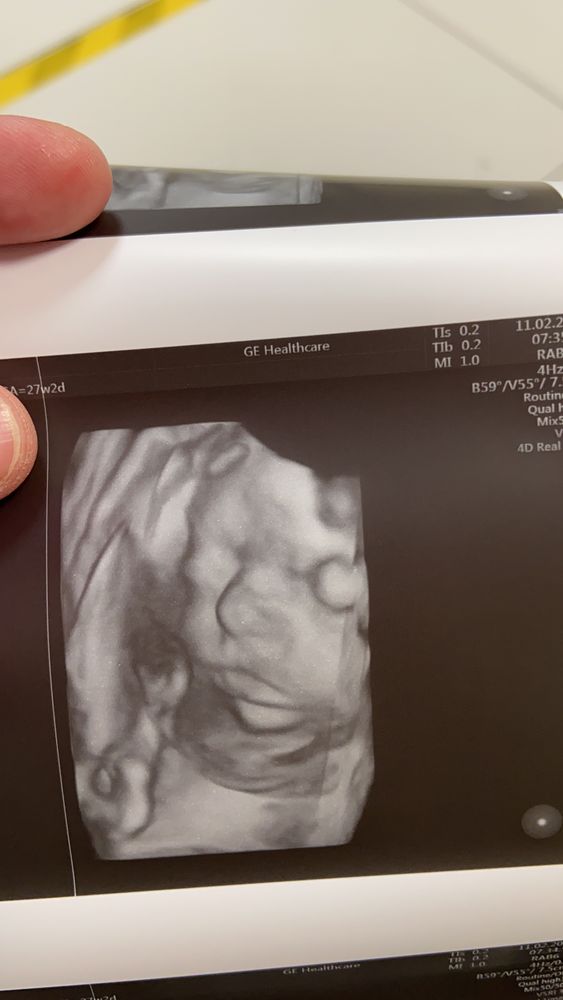

11 февраля 27 недель 2 дня очередное узи с 3д

Все хорошо, малышка подросла, изменилась в лице. Активно зевала и корчила личико. Главное здорова.